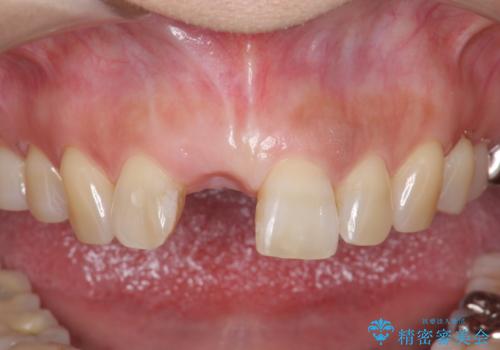

前歯 インプラントによる欠損補綴

- 目立つ一番前の歯を失い、接着剤で応急処置をしていましたが永続性のある修復を希望され来院されました。

入れ歯・ブリッジ・インプラントによる欠損補綴の方法のうち審美的で取り外しがなく隣の歯を削らない治療を望まれたため、インプラントによる審美・機能回復治療を計画します。